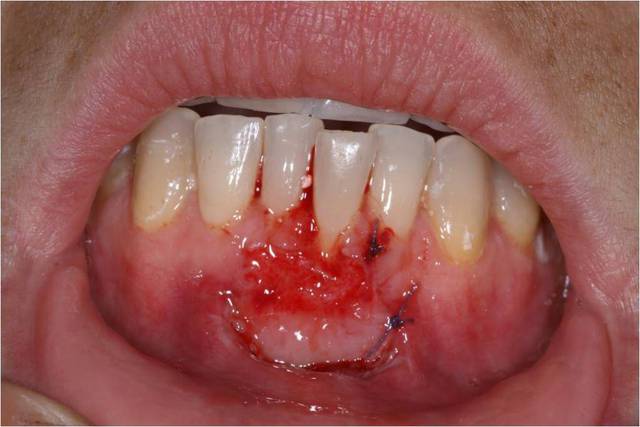

Je me permets de poursuivre ce post car j'ai un échec partiel sur lequel je m'interroge. Est-ce lié à la vestibulisation de l'incisive ? Devrais-je tenter un lambeau déplacé coronairement ?

Reste à faire un lambeau déplacé coronairement.

Sinon, je pense que les sutures auraient pu être différentes, et le greffon placer un peu plus haut.

dudule.. tu as recouvert à la hauteur que tu avais mis ton greffon.. ligne rejoignant gencive 33-43.

D'accord avec céramik, lambeau plus haut et sutures différentes.... mais comment? beaucoup de sutures peuvent nuire à la perfusion du greffon.

Ne pas oublier dent buccalée devient une Cl III de Miller, donc difficile de faire recouvrement complet...